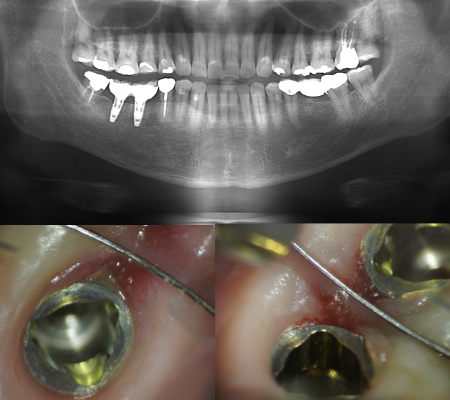

レントゲンとの併用

根管は完璧な清掃を行わなければ、「痛み」「腫れ」が進み、「根尖病巣」という非常に厄介で治りにくい病気にもなります。この病変をしっかり確認するため、根幹治療を行うに際し、レントゲンで根の構造を把握しますが、CT( 三次元立体画像) も利用します。

マイクロスコープ(顕微鏡)治療は特に、根の治療(根管治療)や歯根端切除、修復・充填、かぶせ(インレー・クラウン・ブリッジ)、抜歯等において私には欠かせない右腕となっています。